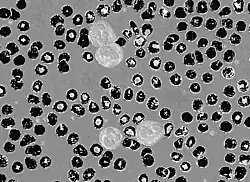

Circular thresholding is an algorithm for automatic image threshold selection in image processing. Most threshold selection algorithms assume that the values (e.g. intensities) lie on a linear scale. However, some quantities such as hue and orientation are a circular quantity, and therefore require circular thresholding algorithms. The example shows that the standard linear version of Otsu's method when applied to the hue channel of an image of blood cells fails to correctly segment the large white blood cells (leukocytes). In contrast the white blood cells are correctly segmented by the circular version of Otsu's method.